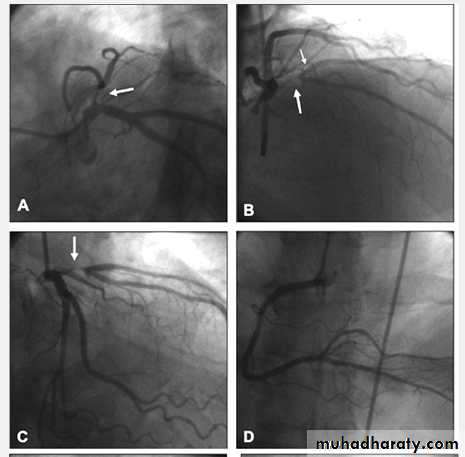

Proximal LAD PCI

CVS

Bifurcational lesion PCI